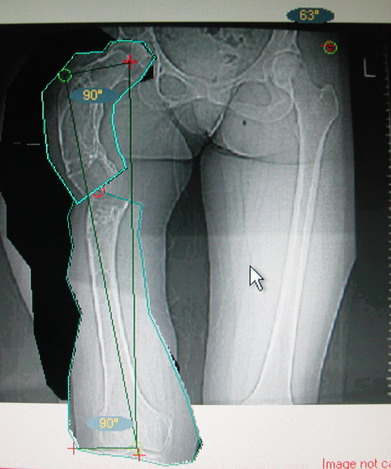

Возможна аппаратная коррекция оси с формированием клиновидного регенерата, которая решила бы и проблему укорочения (что, впрочем, нужно уточнить по схеме, сделанной по рентгенограмме с хорошим захватом смежных суставов - схемка по присланному снимку в приложении). По окончании коррекции - блокируемый стержень, который и сократит время пребывания в аппарате, и вообще возврата к нормальной жизни, а также будет мерой профилактики патологических переломов.

А может быть, если при планировании выяснится, что "открытый клин" решает все проблемы, и есть достаточное приведение в тазобедренном суставе, пойти на одномоментную операцию - чрескожная поперечная остеотомия на вершине деформации и закрытый интрамедуллярный остеосинтез.

Собственно сустав не беспокоит, объем движений полный. По скиаграммам получается, что достаточно одной остеотомии на вершине деформации, чтобы восстановить длину и вывести коленный сустав в нужное положение.

На мой взгляд, для того, чтобы правильно исправить данную деформацию, необходимо обследование больного, которое должно включить в себя, помимо осмотра: 1. Рентгенограммы ( передне-задние и боковые)нижних конечностей на всю длину стоя . 2. Компьютерная томография для измерения длины нижних конечностей. 3. Комьютерная томография тазобедоенных, коленных и голеностопных суставов для измерения углов антеверсии тазобедренных суставов и ротации голеней. Это тот минимум, который должен входить в предоперационное обследование каждого больного с тяжёлыми формами деформаций конечностей.

Поскольку в данном случае имеется дело с довольно большой деформацией с укорочением, одномоментная её устранение с внутренней фиксацией, чревато с одной стороны неправильной коррекцией, с другой, нейроваскулярными осложнениями.

Моё мнение, что двойная остеотомия бедра с аппаратом Илизарова + Гексаподный механизм, или Тэйлора, В данной ситуации является методом выбора. Я очень извеняюсь за качество прилагаемых снимков, в которых я постарался отразить разницу междe одной и двумя остеотомиями бедра.